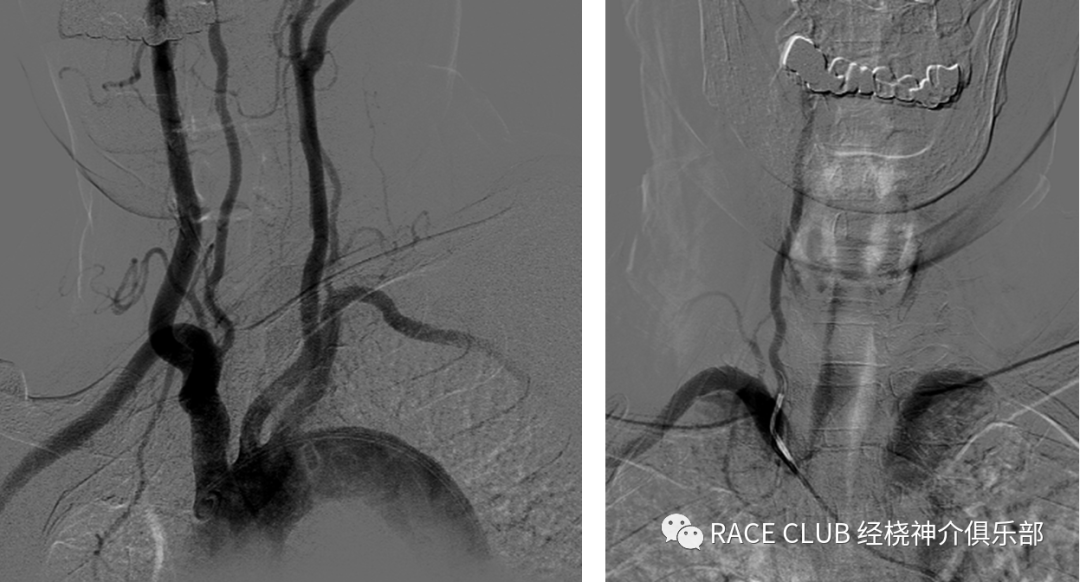

弓上造影(股动脉入路)

接三通、y阀,排气 •接上单弯导管或西蒙导管排水

•透视下推床,露出升主动脉

•进泥鳅导丝,将猪尾导管头端拉直,一起退出

•将单弯导管或西蒙导管头端送入血管鞘内,泥鳅导丝浸水后从y阀送入,透视下将导管导入,分别进入右锁骨下动脉、双侧颈总动脉(颈内动脉)、左锁骨下动脉造影

造影导丝是什么全脑血管造影术_https://www.jmylbn.com_新闻资讯_第11张

•侧位:(42)上端去头皮,下端露出分叉处,最好看到导管头端,图像在正中间

•正位:(27或31)矢状缝对齐,汤氏位,错开眉弓对大脑中动脉影响

造影导丝是什么全脑血管造影术_https://www.jmylbn.com_新闻资讯_第12张

•正位:(48)矢状缝对齐,稍汤氏位,上端平人字缝,下端露出椎动脉开口,看到导管头

•侧位:(31)左侧平枕骨隆突,下平2/3椎体